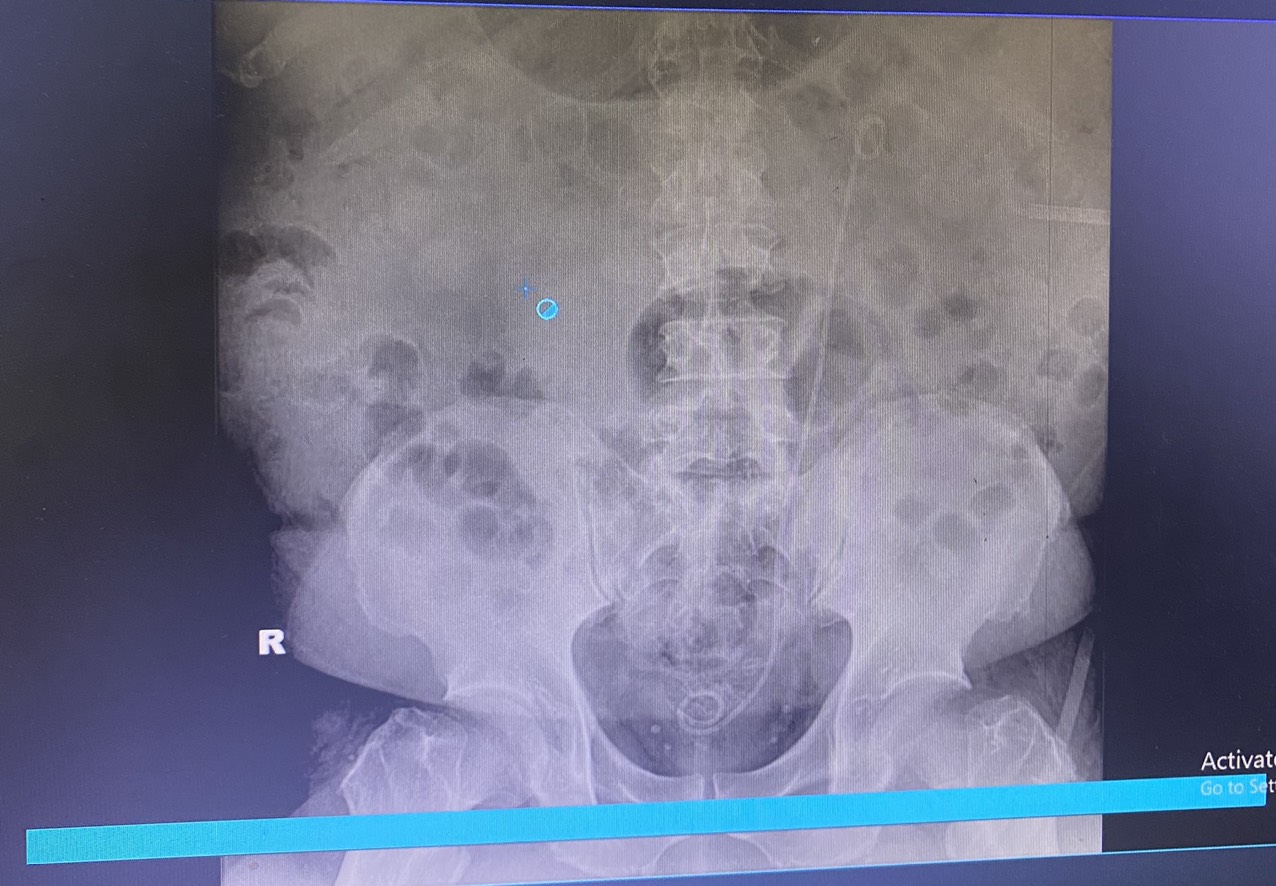

Bệnh nhân nam 48 tuổi biết mình có sỏi thận mấy năm nay nhưng không theo dõi hay điều trị. Chỉ đến khi bị xuất huyết tiêu hóa mới vào viện thăm khám và bác sĩ Bệnh viện đa khoa Quốc tế Hải Phòng phát hiện viên sỏi của bệnh nhân với kích thước 4cm đã bắt đầu gây biến chứng làm giãn thận và suy thận. Tình huống này, nếu không được can thiệp kịp thời dễ dẫn đến nguy cơ nhiễm trùng, suy thận, ảnh hưởng đến tính mạng của người bệnh.

Xác định rõ tình trạng bệnh của bệnh nhân kết hợp người bệnh có thể trạng béo phì (nặng 120kg) cùng nhiều bệnh lý phối hợp như đái tháo đường, viêm loét đường tiêu hóa, rối loạn lipid máu, nguy cơ tắc mạch… bác sĩ Khoa Ngoại thận tiết niệu – Nam học đã phải tiến hành hội chẩn, đánh giá rất kĩ lưỡng và cân nhắc lựa chọn phương pháp điều trị tối ưu nhất cho bệnh nhân là sau khi điều trị ổn định tình trạng xuất huyết tiêu hóa, sẽ tiến hành tán sỏi qua da bằng đường hầm nhỏ. Quá trình phẫu thuật gặp nhiều khó khăn về gây mê, gây tê do bệnh nhân béo phì, cổ ngắn, khó đặt tư thế và tìm đường vào thận song ekip phẫu thuật đã khéo léo tạo đường hầm qua da, sử dụng năng lượng laser phá vỡ sỏi thành mảnh nhỏ để lấy ra ngoài. Kết quả, đã xử lý hết sỏi sau một lần tán, phẫu thuật đảm bảo an toàn, hiệu quả. Đến nay, người bệnh đã hồi phục và xuất viện.

Theo TS.BSNT Phạm Việt Hà – Giám đốc chuyên môn phụ trách hệ Ngoại Bệnh viện đa khoa Quốc tế Hải Phòng cho biết: Phẫu thuật tán sỏi qua da hiện nay đã dần thay thế cho phẫu thuật mổ mở. Ở bệnh nhân này thể trạng béo phì với kích thước của viên sỏi lớn như vậy thì như trước đây, người bệnh sẽ phải chịu một cuộc mổ mở với nhiều đau đớn, vết mổ rất dài lên đến 30 đến 40 cm, nguy cơ biến chứng cao, thời gian phục hồi lâu và phẫu thuật viên cũng phải rất vất vả vì tổ chức mỡ dính xung quanh thận nhiều, phẫu tích để tiếp cận sỏi rất khó và nhiều nguy cơ nhiễm trùng, gây tổn thương phần mềm xung quanh, song hiện nay với việc áp dụng phương pháp kỹ thuật cao – phẫu thuật tán sỏi qua da, đã khắc phục được những nhược điểm của mổ mở. Phương pháp này có ưu điểm là can thiệp xâm lấn tối thiểu (như trường hợp này vết mổ chỉ kéo dài 1cm) nhưng mang lại hiệu quả tối đa. Tán sỏi qua da chỉ với vết rạch rất nhỏ nên người bệnh nhanh bình phục và sớm trở lại sinh hoạt bình thường. Phẫu thuật tán sỏi qua da đã được thực hiện tốt ở bệnh nhân này nhưng do thể trạng người bệnh béo phì, thừa cân nên việc tạo đường hầm vào thận gặp khó khăn, đường hầm rất dài lên tới 13 cm, khi đưa ống soi vào bể thận thì chiều dài ngập hết ống đỡ … chính vì vậy nên tán sỏi và lấy mảnh vụn sỏi ra cũng rất khó và mất nhiều thời gian hơn so với các bệnh nhân khác.